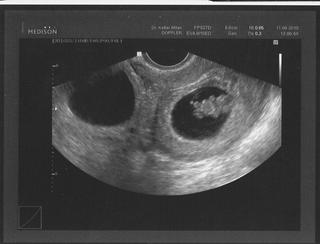

to druhé je cysta z vaječníku, to není gestační váček, toho druhyho mi už nefotila, jsem strašně štastná i za toho jednoho 😵 😵 😵

Holky stejně je to zvláštní, že do mě vložila 200% embryjka a oba měli v šestém týdnu srdíčka. Myslela jsem že už je všechno stopro a ono ne. 😒 Ale prý už se nemusím bát o tohle 😵 tak si ho budu mooooc hyčkat.

@stanuskaa jojo zatím tam jsou dvě, jsem po ivf, tak proto. jak to myslíš, jestli bych nezměnila status? nějak jsem nepochopila smysl otázky. ☹